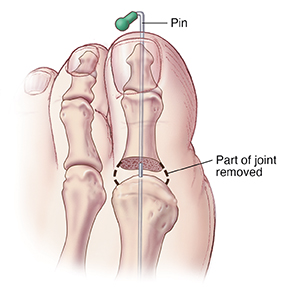

Arthroplasty

During surgery, bone growth and arthritis are trimmed, and part of the joint is removed. A pin can be used to align the bones and to keep them from touching. The pin is removed after several weeks. In some cases, the entire joint or part of the joint may be replaced with an implant. You may have to wear a splint or a surgical shoe for several weeks. When healed, the bones become connected with scar tissue.